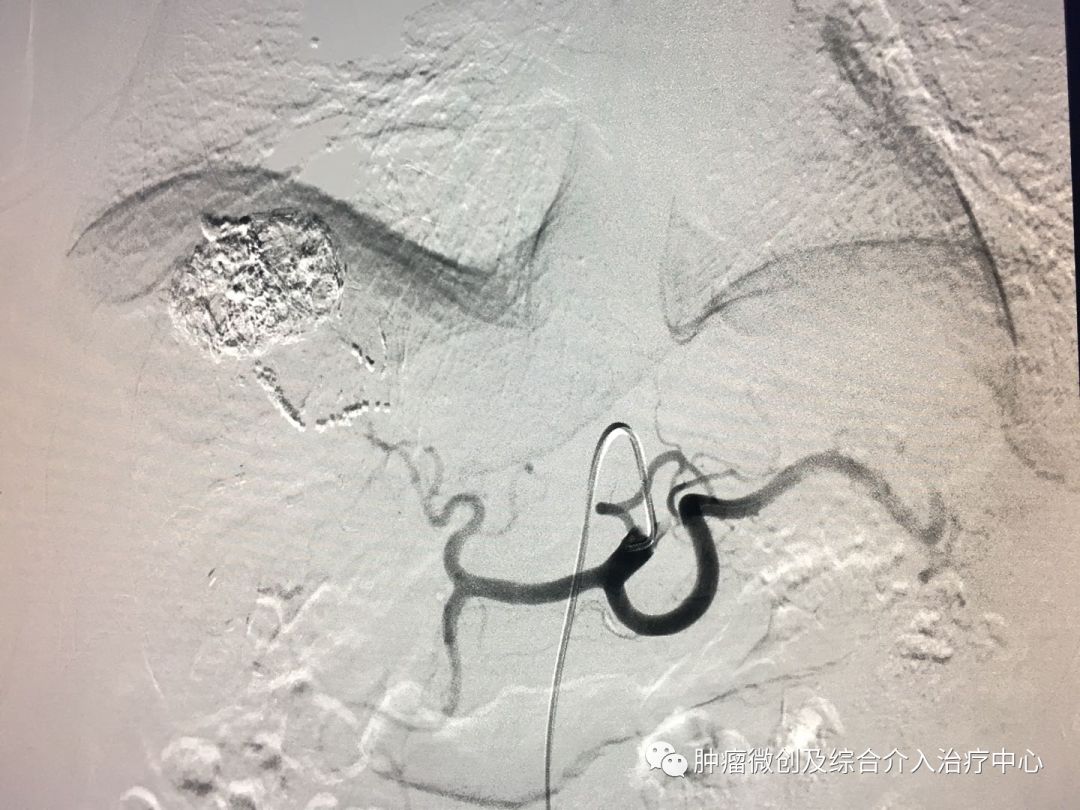

(鼻咽癌颈部转移瘤破溃出血,DSA造影提示左颈部病变血管迂曲、紊乱,内有出血)

(介入栓塞病变血管后,DSA示肿瘤病变血管栓塞好,血管走向清晰,出血停止)项目介绍:头颈部良、恶性肿瘤临床常见,其良性见于鼻咽纤维血管瘤,恶性者见于鼻咽、鼻窦癌,颈部转移性肿瘤等; 传统止血治疗疗效有限,给患者及家属带来极大的精神压力,介入手术栓塞病变血管可达到确切的止血效果,并致病变缺血萎缩。04急性肺栓塞介入手术治疗